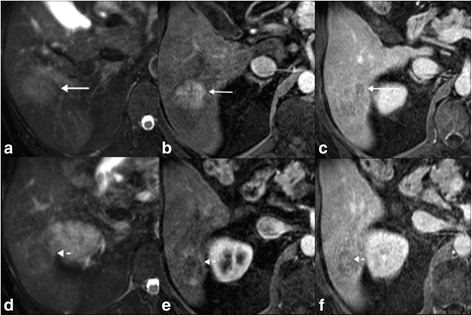

There were also other features associated with HCC in the cHCC-CC group: n = 2 had intra-lesional fat and n = 4 had intra-lesional hemorrhage. While these features are highly specific in differentiating cHCC-CC from ICC, the low sensitivity does not help in differentiating cHCC-CC from ICC. In 3 cases of cHCC-CC there was both washout and progression in the same lesion (Fig. 4), which does differentiate cHCC-CC from ICC, as washout is not seen in ICC. These features can be seen in scirrhous HCC, but this should alert the radiologist to the possibility of a cHCC-CC tumor and consideration for biopsy as the potential treatment options for these two tumors vary [27, 28].

Pathologically proven cHCC-CC tumor demonstrating both washout and progression: a-c is the superior aspect of the tumor and d-f is the more inferior aspect of the tumor. The superior portion of the tumor is T2 intermediate (a) and shows show arterial hyperenhancement and washout (b, c), typical of HCC. However the more inferior component of the tumor has some internal T2 hypointense components (d), and relatively hypovascular on the arterial phase (e) and shows some progression of enhancement on the delayed phase (f). The presence of washout and progression in the same lesion should alert the radiologist to the possibility of a cHCC-CC tumor